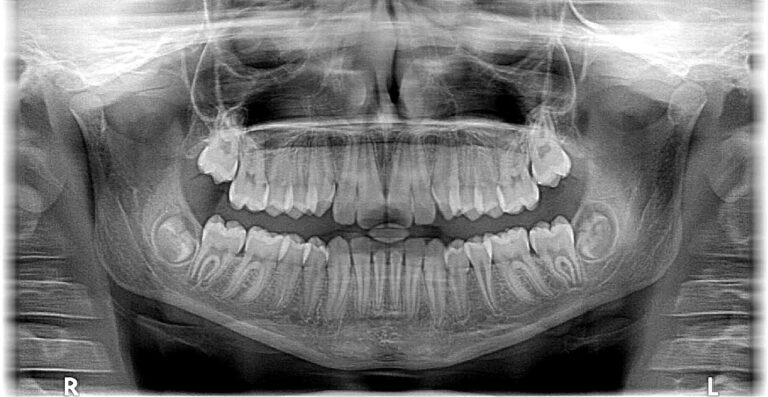

Kiedy i dlaczego stomatolog może zlecić wykonanie RTG zęba?

RTG zęba

Stomatolog może zlecić wykonanie RTG zęba w różnych sytuacjach, w celu dokładnej diagnozy i oceny stanu jamy ustnej. Trafna diagnoza oraz wnikliwa analiza stanu uzębienia to klucz do zdrowego uśmiechu. Co ważne, badanie jest bezbolesne, bezinwazyjne oraz całkowicie bezpieczne.  …